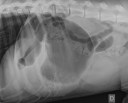

RadioQuiz 2: Tordu ou pas cet estomac ?